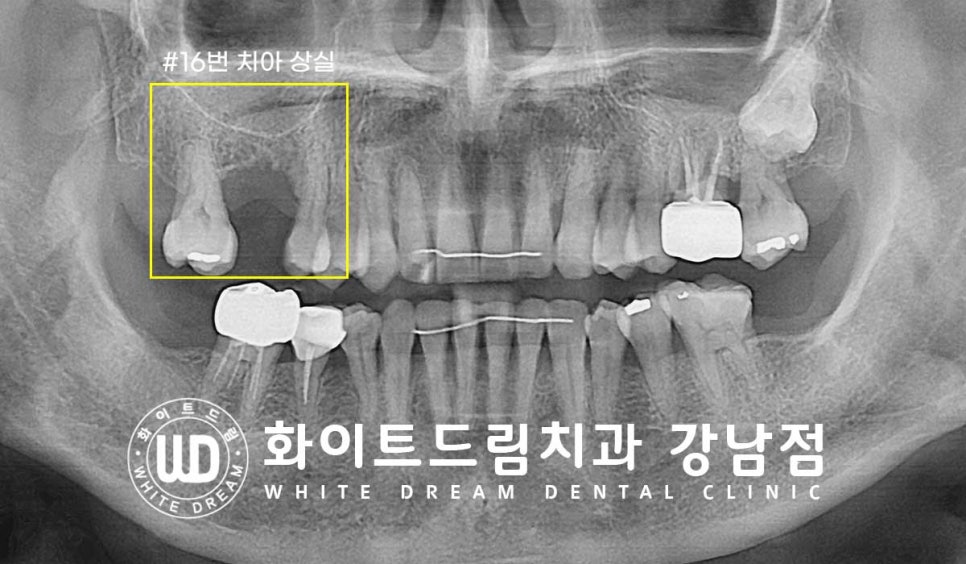

▲ 16번 어금니를 발치한지 1년 정도 되신 환자분이신데

골폭이 주위 치아가 있는 부위와 다르게 움푹 들어가 있는 것이 확인됩니다.

골 두께가 줄어든 만큼 골 길이는 얼마나 줄었을까요?

치료 전 X-RAY를 보면서 이야기 이어가 보겠습니다.

▲ 상실된 16번 치아 부위입니다.

1년 사이에 잇몸뼈 흡수가 많이 진행된 것이 확인됩니다.

기존에 잇몸 염증으로 치아를 발치하게 되었다고 하셨는데

이전에 염증으로 잇몸뼈가 많이 소실된 상태 + 발치 후 1년 방치로 인한 골 흡수

가 함께 진행되었기에 이렇게 잇몸뼈가 얼마 남지 않은 것으로 추정되었습니다.